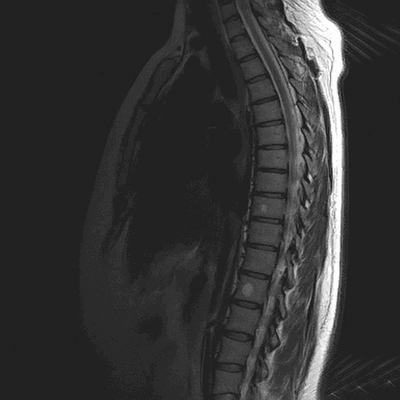

Расшифровка МРТ позвоночника

Гемангиомы на магнитно-резонансной томографии грудного отдела позвоночника (сагиттальная проекция, Т2 взвешенная последовательность)

МРТ позвоночника - высокоинформативный метод диагностики, использующий для построения детальных изображений структур области интереса свойства магнитного поля, радиоволны и компьютерную обработку. По показаниям исследование выполняют с контрастным усилением: в вену вводят препарат, содержащий хелаты гадолиния.

Как выглядит фото-снимок МРТ позвоночника

МРТ грудного отдела позвоночника (сагиттальная проекция, Т1 ВИ)

Магнитно-резонансные томограммы отображают внутренние структуры зоны интереса в трех плоскостях. Каждый снимок представляет собой один срез, на распечатанном фото МРТ их несколько.

В норме позвонки гладкие, повреждения отсутствуют. Фиброзно-хрящевые диски, выполняющие роль амортизаторов, не выпячиваются, имеют стандартную высоту, без признаков дегенерации. Спинной мозг выглядит на фото как белый шнур без видимых перекосов и других изменений.